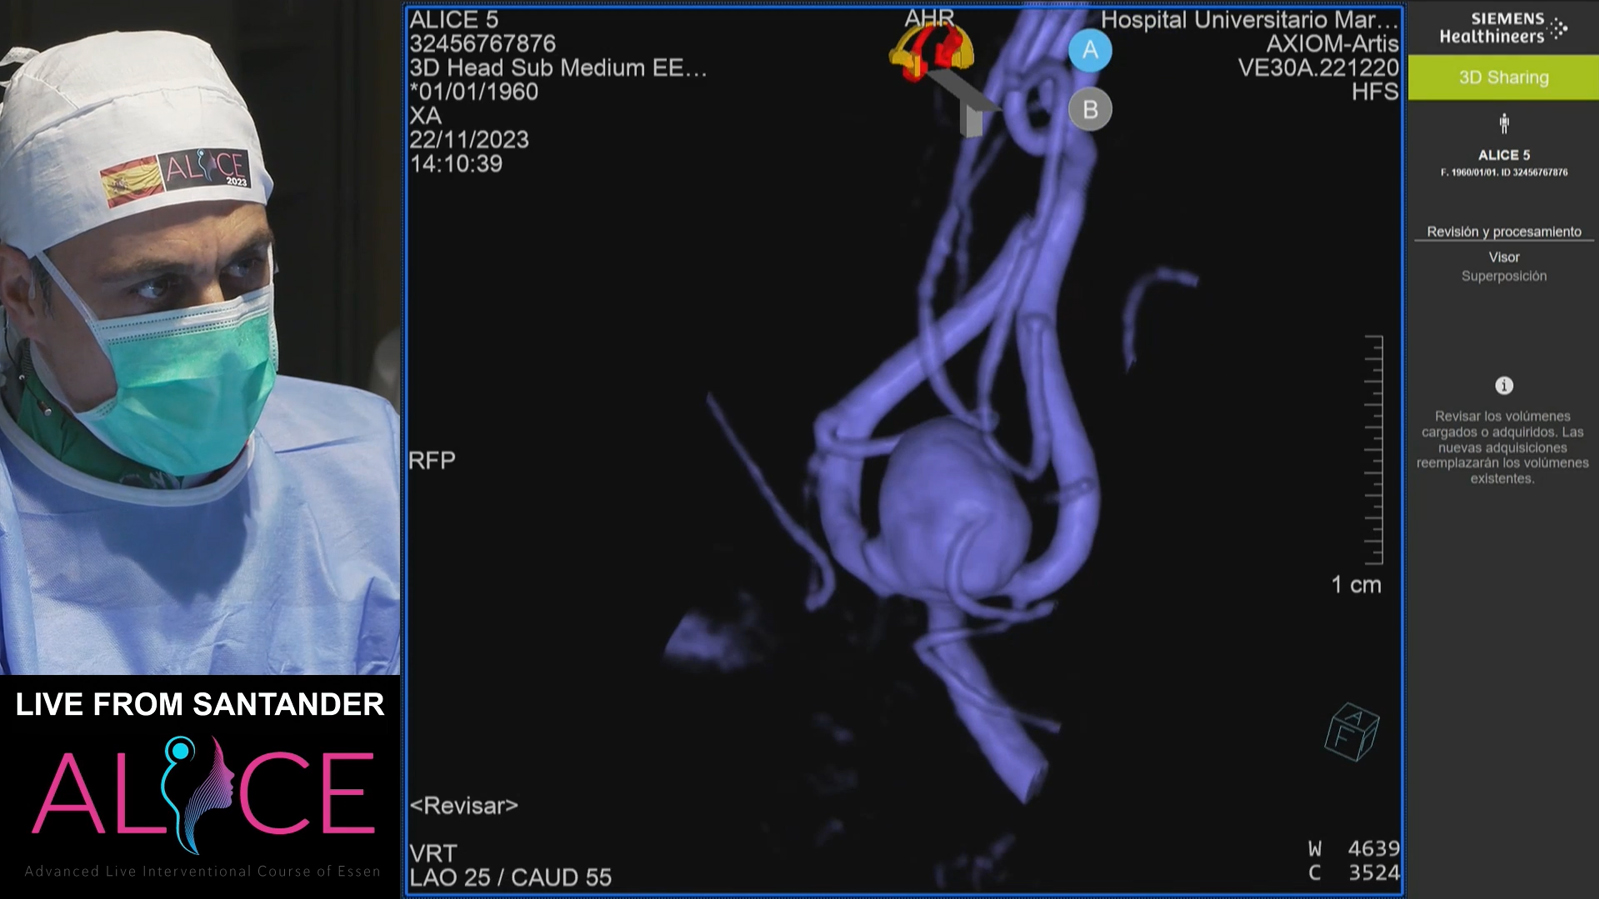

from Santander: Aneurysm

MCA Aneurysm

MCA aneurysm, kissing balloons for understanding of anatomy